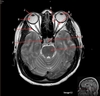

A

Genu Corpus Callosum

B

Splenium Corpus Callosum

C

Pons

D

Cerebellum

Image weighting and axis

T2 Flair

Sagittal